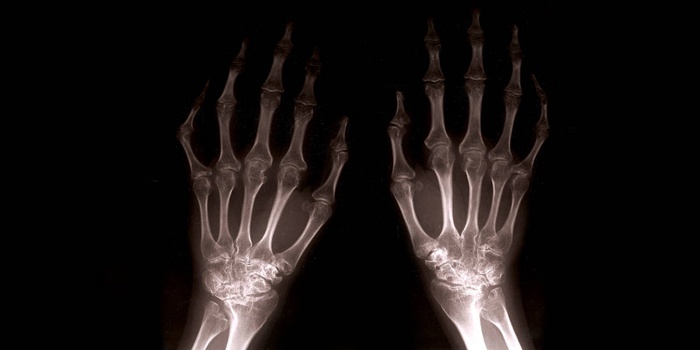

- Поверхность фаланг пальцев, оставшись без смазки, разрушается. Происходит «перерождение» костной ткани, образуются остеофиты – наросты, заметные на рентгеновском снимке.

- Характеризуется неподвижностью суставов, которые сильно разрушены. Остеофиты наглядно видны, образуя узелковые наросты: проксимальные (сбоку сустава) – Бушара, дистальные – Гебердена.

- Рентген. На основании данных рентгенографии доктор устанавливает степень поражения мелких суставов и стадию развития болезни.